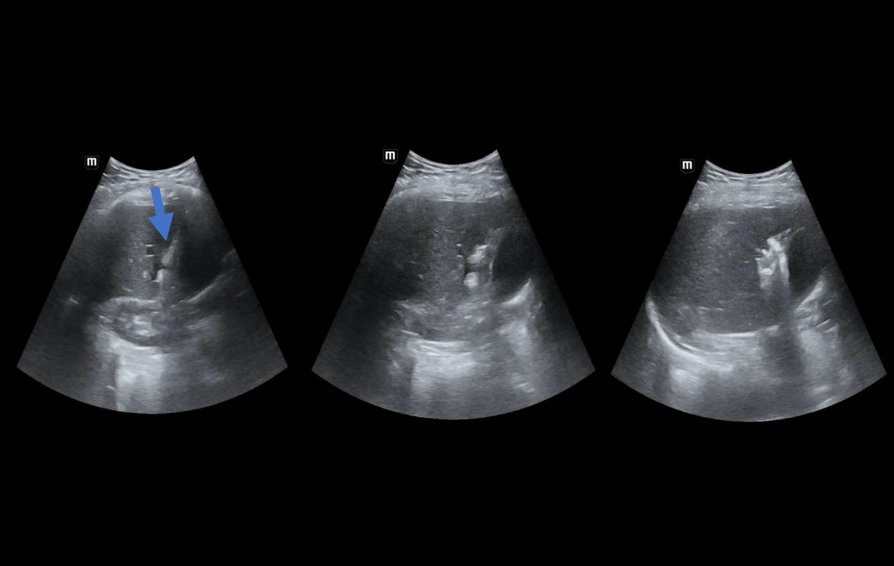

Ultrasound Journal 26 - Evaluation of the percutaneous radio-frequency thermal ablation zone using CEUS

According to the available reference literature, recurrence in the lesion zone after thermal ablation in the liver occurs in approximately 12% of cases [1]. Based on the analysis of factors influencing the local recurrence post-thermal ablation, the relations to the adjacent vessels were listed. Both the size of the adjacent vessel and the absolute distance between the ablation zone and any near vessels affect the risk of recurrence in the treated area [2]. In this case, during the ablation procedure, the blood flow in the hepatic vein decreased the temperature in the area of thermal ablation, which directly reduced the effectiveness of the procedure in the area affected by high-frequency current. CEUS is a good tool for assessing the post-thermal ablation zone, among others, intraoperatively. Its first day sensitivity and specificity are comparable to CT [3]. For CEUS, the criteria for thermal ablation failure or local recurrence include irregular enhancement in the arterial phase and contrast washout in the portal phase [4].